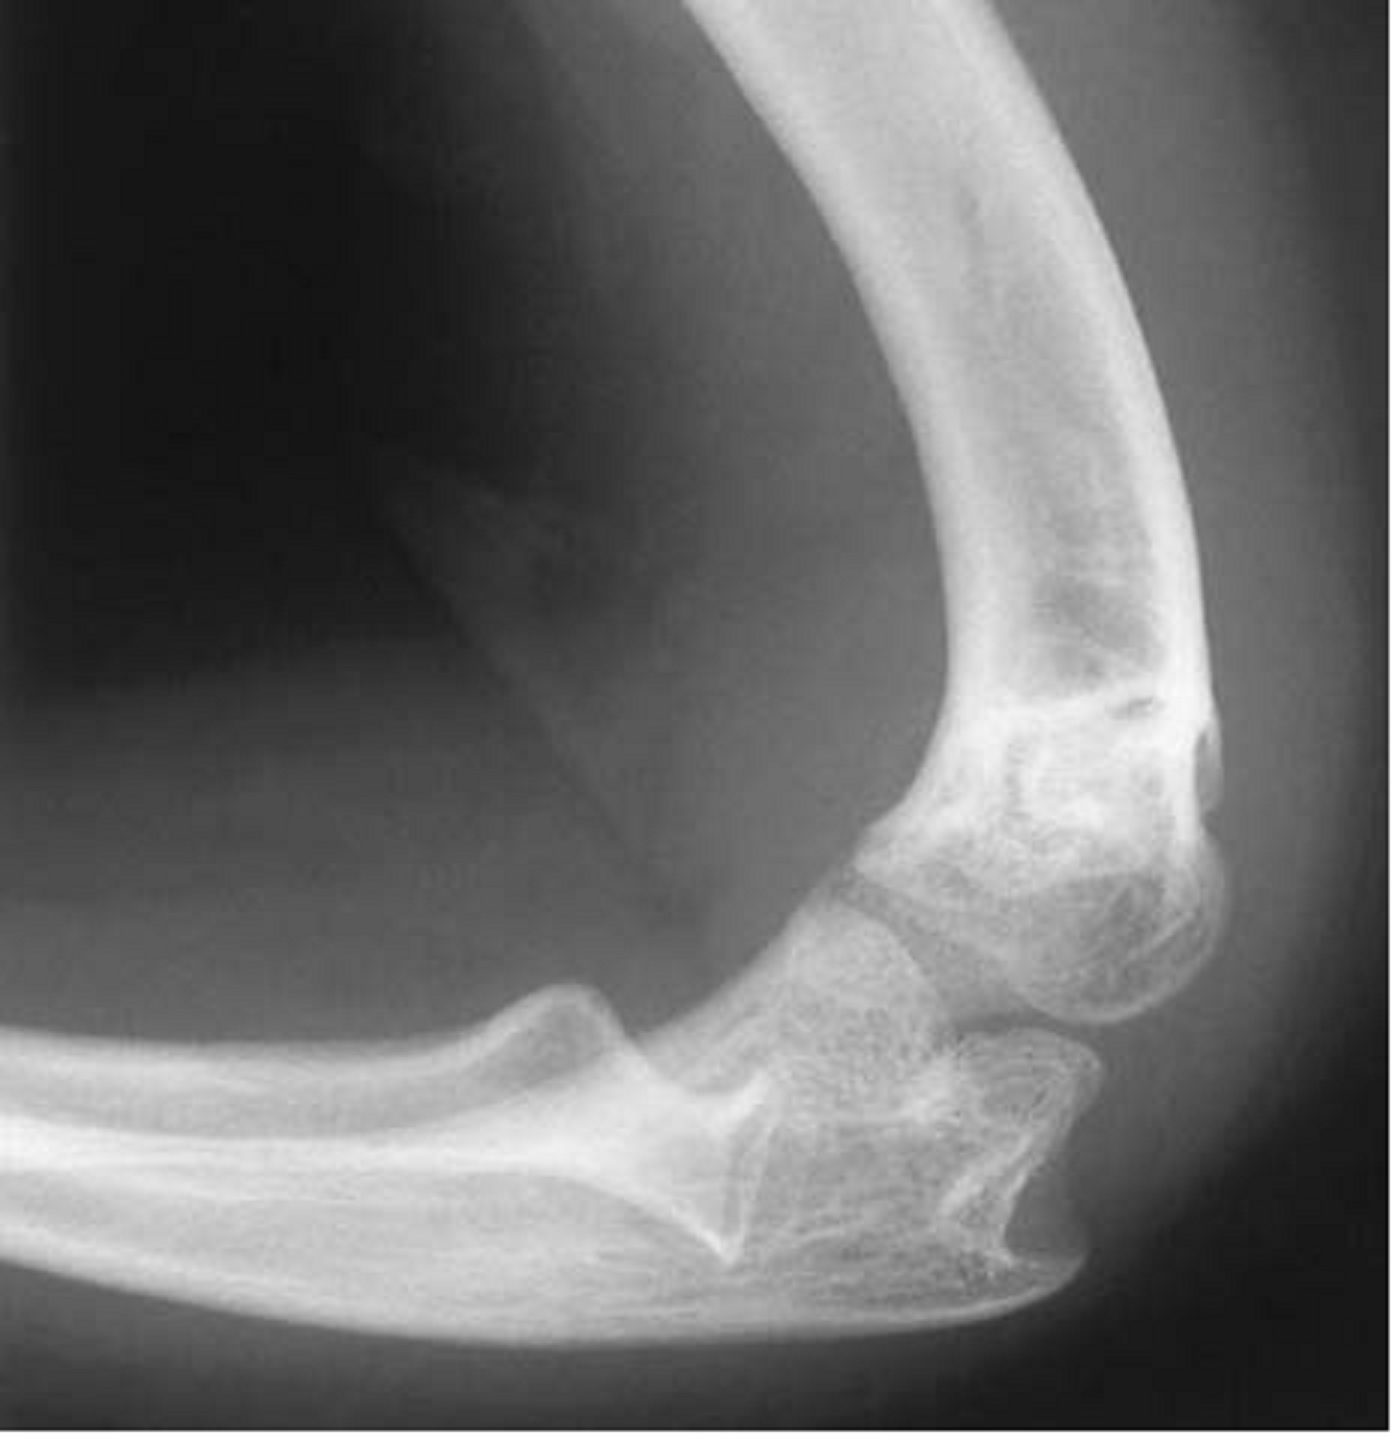

| Deformidades del codo en la acondroplasia. Radiografía lateral del codo de una niña de ocho años con acondroplasia. Se observa arqueamiento posterior del húmero distal y dislocación posterior de la cabeza del radio. Créditos: Hiroshi Kitoh et al, 2002. |

La inclinación posterior de la porción distal del húmero fue una anomalía radiológica constante y cuando fue mayor a 20° dio lugar a una pérdida en la extensión. En este estudio hay una nota bastante relevante: la restricción en la extensión del codo, incluso cuando la función del hombro es normal, puede causar deterioro funcional de un brazo corto.

Bailey afirmó que las deformidades de la cabeza del radio, con o sin dislocación, eran normalmente la causa de la pérdida de la extensión. Nuestro estudio proporciona evidencia adicional para vincular la dislocación con una pérdida más grave de la extensión completa. El cóndilo humeral hipoplásico observado en la acondroplasia sugiere que la dislocación es congénita.

Un cúbito pequeño en los antebrazos y un peroné más largo en las extremidades inferiores son hallazgos radiológicos comunes, probablemente como resultado de tasas de crecimiento desiguales. El crecimiento excesivo del radio, cuando se asocia con una longitud reducida del cúbito, puede provocar una dislocación congénita de la cabeza del radio.